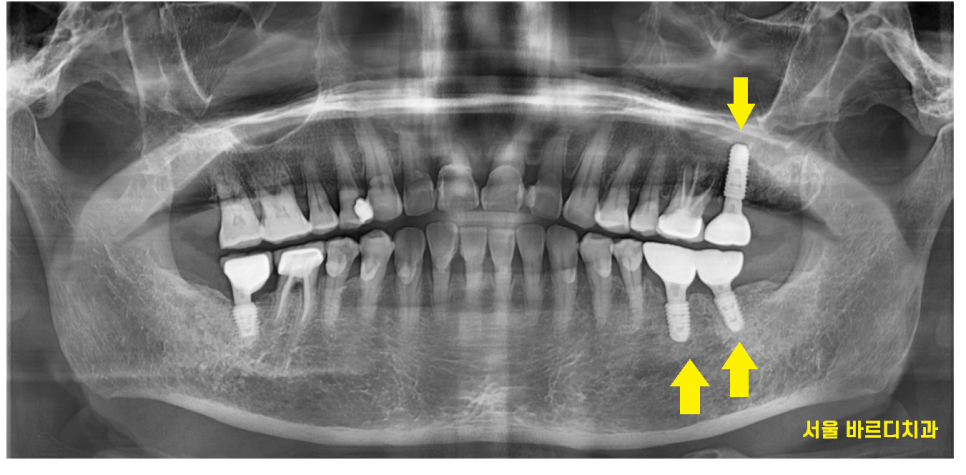

일반적으로 임플란트가 완성되는데 소요되는 기간

윗 어금니의 경우 4~6개월

아래 치아는 2~3개월 입니다.

어금니 흔들림과 통증이 동반되어

먼저 발치한 윗니

고덕동 치과에서 임플란트를 시행

24.02.16

2개월 뒤 아래 치아 수술도

고덕동 치과에서 임플란트 완료하였습니다.

24.05.08

수술 시점은 달랐지만

윗니 아랫니 완성은 한번에 해드렸는데요.

고덕동 임플란트 완성사진입니다.